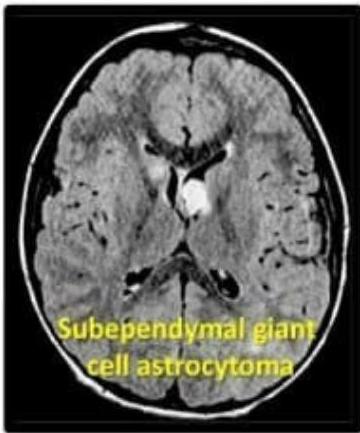

- Subependymal Giant Cell Astrocytoma (SEGA): Can cause obstruction of CSF outflow Hydrocephalus.

- Subependymal giant cell astrocytoma (SEGA)

Diagnosis: Based on characteristic lesions, seizures, intellectual deficit, and visceral tumors. Neuroimaging (MRI) demonstrates subependymal-calcified nodules.